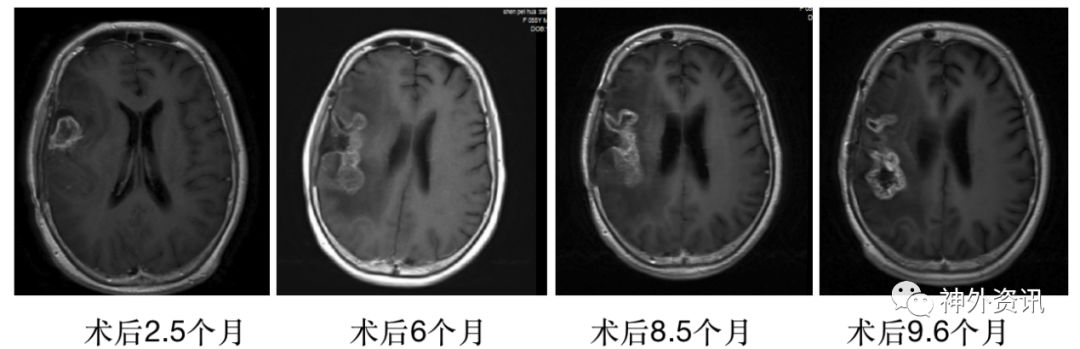

术后2.5个月(图5)可见术腔异常增强病灶,经MDT门诊讨论,认为放疗过程中或者放疗刚结束的增强病灶通常考虑假性进展,建议继续服用替莫唑胺。每3个月影像学随访,术后6个月增强病灶增大,此后增大不明显(图5)。

![]()

图5. 术后序贯磁共振影像:术后2.5个月,在手术区域出现增强结节,术后6个月增强部分增大,术后9.6个月进一步增大。